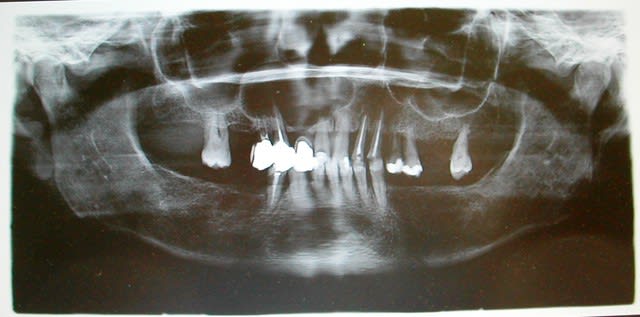

Patiente vue en juillet 2010 avec découverte sur une rétroalvéolaire d'un kyste maxillaire au dépend de 11, on n'y voit évidement qu'une partie du kyste. Panoramique demandé dans la foulée, à la vue de la radio,je l'adresse à mon stomato préféré, reçue en aout 2010 et intervention prévue mi septembre 2010. Quelque jours avant l'intervention elle annule tout.

Je la revois hier pour mettre un peu de résine sur la 11, ça la gratte un peu. Je refuse et insiste pour qu'elle se fasse soigner ce kyste. Elle me répond qu'elle a pas les moyens de faire la prothèse provisoire immédiate que je lui avait proposé après énucléation du kyste et l'extraction des dents qui le jouxtent, à savoir 14,13,11. J'ai oublié de dire qu'elle bénéficie de la CMU et la prothèse immédiate n'est pas prévue dans le cadre CMU. Elle m'a dit texto " J'ai autre chose à foutre que de mettre 300 € dans un appareil provisoire!"